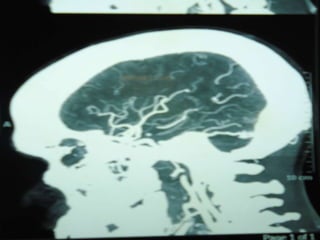

Cerebral angiography provides definitive diagnosis. It documents a functional AV shunt; however, because it is an invasive test, it is not performed as the first imaging study. Cerebral angiography also allows grading of the AVM via the following Spetzler and Martin criteria.

Cerebral angiography providesdefinitive diagnosis. It documents a functional AV shunt; however, because it is an invasive test, it is not performed as the first imaging study. Cerebral angiography also allows grading of the AVM via the following Spetzler and Martin criteria.